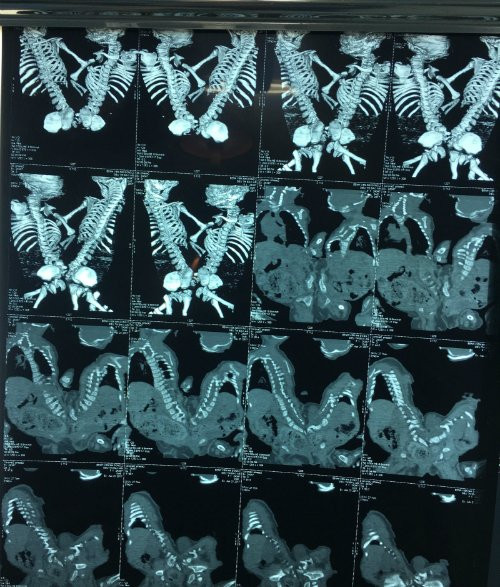

Tình trạng dính nhau của hai cháu bé trước mổ. (Ảnh do bệnh viện cung cấp)